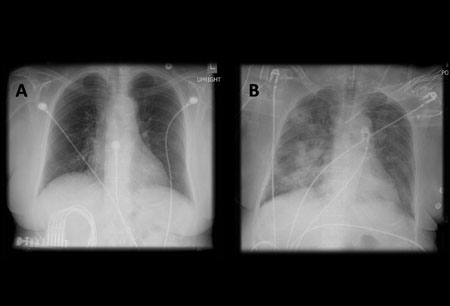

- chest x-ray